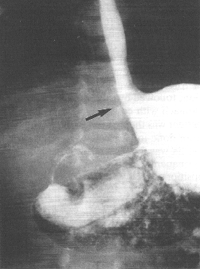

Case 32.3. F.V., male aged 75 years, was admitted for mild obstructive jaundice of 10 days' duration. There had been colicky epigastric pain for the previous 5 months, as well as acidity and heartburn for years. Oral and intravenous cholecystography revealed poor concentration of the opaque medium with calculi in the gallbladder and a dilated common bile duct containing stones. (At the time sonography of the gall bladder had not been perfected). The radiological examination showed a large, irreducible hiatus hernia (Fig. 32.3). A contraction of the pyloric sphincteric cylinder, 4.5 cm in length, with a tendency toward formation of a pseudodiverticulum on its greater curvature side, was constantly present; there was no evidence of any other lesion locally or in the remainder of the stomach. The diagnosis of contracted pyloric sphincteric cylinder, resembling AHPS, in association with hiatus hernia was made. At operation a cholecystectomy was done and calculi were removed from the common bile duct. The surgeon stated that the pyloric area of the exposed stomach felt a little thicker than usual. Had his attention not been drawn to it beforehand, it is doubtful if he would have commented on it in his operative notes. No other gastric lesion was detected. Because of the patient's age, it was decided not to repair the hernia at that time. Repeat radiographic examination 5 months later showed the irreducible hiatus hernia and the contracted pyloric sphincteric cylinder to be unchanged.

| Fig. 32.3. Case F.V. Large irreducible hiatus hernia (black arrow). Contracted pyloric sphincteric cylinder |